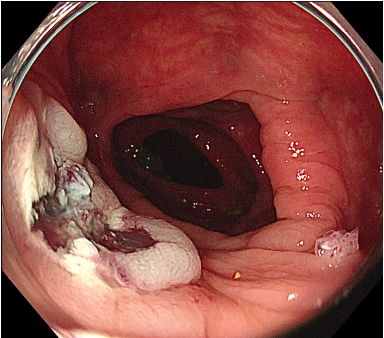

図3: スネアで絞扼し切除(サンプル)

図3. スネアを絞扼し、そのまま切除します。写真は切除後の創部です。